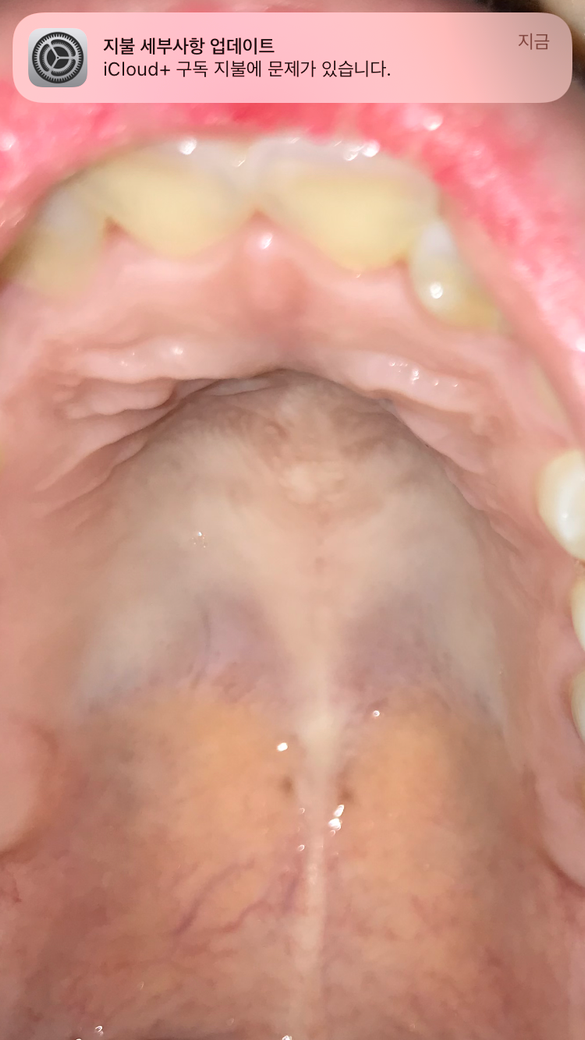

입천장이 너무 아픈데 입천장좀 봐주세요 (사진 첨부)

요즘 입 천장이 얼얼하고 아픈데 사진을 찍어보니까 너무 하애서요 원래 이런 색이 맞나요…?ㅠㅠㅠㅠ 그리고 요즘 혀도 아픈데 구강암 초기증상이라고 떠서 너무 무섭네요….

입천장 색이 이상한 것 같아 걱정스러우시군요. 사진으로 보이는 구강에서 이상이 보이지는 않는데, 가까운 이비인후과에서 상담받아보시는 것을 권해드리고 싶습니다.

올려주신 사진만 보면 특별한 이상은 없다고 생각됩니다. 혀도 별로 이상 없어 보이는데요. 따뜻한 물을 자주 드시면서 관리해 보시기 바랍니다.